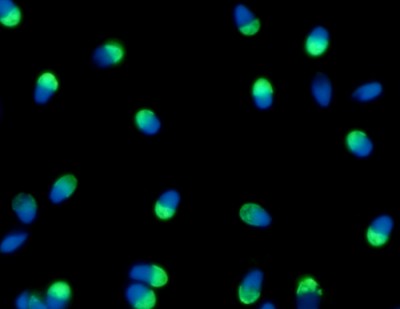

Implementan en la Argentina una novedosa técnica que selecciona los espermatozoides sanos , ya hubo más de cien nacimientos

El grupo de trabajo de la doctora Vanesa Rawe fue de los primeros en Argentina en implementar una novedosa tecnología llamada “Columnas de Anexinas V” que selecciona espermatozoides de buena calidad desde una...